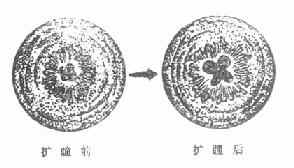

(6)虹膜后粘连:渗出物聚积于虹膜与晶状体间的缝隙中,极易形成粘连。急生期粘连范围小,程度轻,经用强力散瞳剂可以拉开,渗出物吸收后,瞳孔可复圆,但在晶体表面常遗留环形色素斑。如渗出物机化,仅部分被拉开,则瞳孔参差不齐呈花瓣状。(图8-2,8-3)。

图8-2 部分虹膜后粘连

图8-3 虹膜后粘连散瞳前后